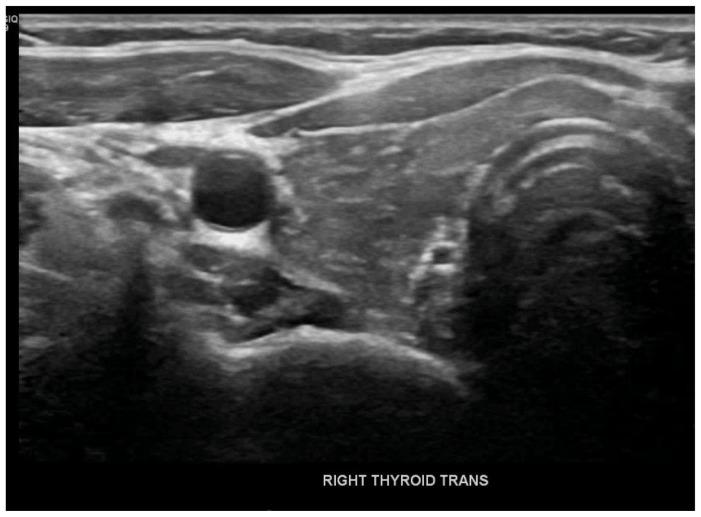

Immune Checkpoint inhibitors (ICIs) such as nivolumab, pembrolizumab, and ipilimumab are monoclonal antibodies against cytotoxic T lymphocyte antigen 4 (CTLA4) or program death (PD)1 and its ligand PDL1. Agents targeting PD1, such as pembrolizumab, have shown widespread efficacy in the past and are also associated with a wide range of immune-related adverse events (irAEs), including endocrine toxicities. A 31-year-old female with a medical history significant for Stage IIb Breast cancer on chemo and immunotherapy (pembrolizumab) presented with nausea, vomiting, and generalized abdominal pain. Laboratory studies showed a blood glucose level of 356 mg/dl, elevated Anion gap 18 meq/L, beta-hydroxybutyrate 46 mg/d, and low C-peptide levels <0.10 ng/ml. The patient was treated for Diabetic Ketoacidosis (DKA). Further testing revealed high Thyroid Stimulating Hormone (TSH) levels along with elevated thyroid peroxidase levels of 38 IU/L. After discharge from the hospital on insulin and levothyroxine therapy, the patient reported increasing fatigue and further testing revealed low cortisol levels <0.5 mcg/dl with elevated ACTH consistent with primary adrenal insufficiency. The patient was started on hydrocortisone therapy with improvement in symptoms. Endocrine toxicities are not uncommon in patients receiving pembrolizumab, but polyendocrinopathy in a relatively rare side effect of pembrolizumab. Only a few cases of pembrolizumab-induced polyendocrinopathy have been reported so far which we have mentioned in this article. While patients are on immunotherapy, close monitoring for clinical signs & symptoms can lead to an early diagnosis, substantially improving morbidity and mortality.